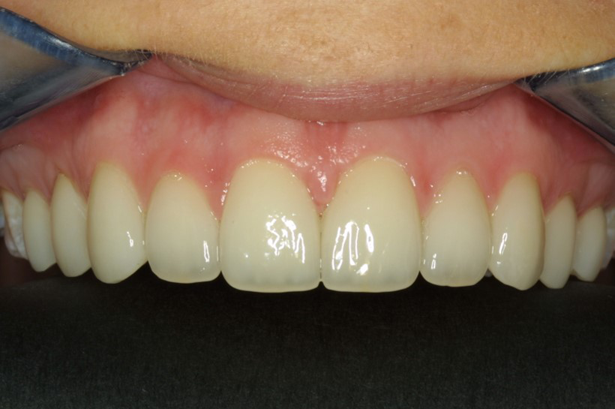

Here is a case where the tissue has been recontoured before veneer preparation (Fig. 5), and during this same appointment the equi-gingival veneer preparations were finished and impressions were done. A few weeks later the veneers were placed and Figure 6 shows the predictability in tissue position.

Fig. 5 Fig. 6